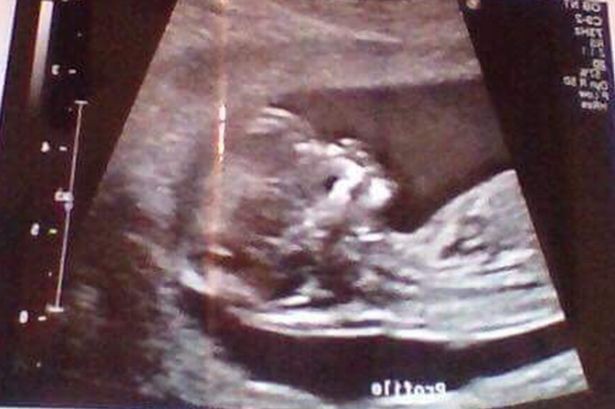

"Tôi cảm thấy rất khó chịu khi ai đó đưa ra nhận xét như vậy. Nhưng sau khi tôi cho họ xem hình ảnh siêu âm, tất cả đều ngạc nhiên. Thực tế là cả tôi và em bé đều hoàn toàn khỏe mạnh" - Reanna chia sẻ.